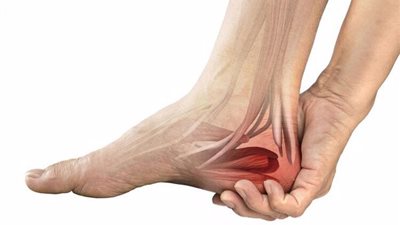

إصابة علي معلول.. ما مضاعفات قطع وتر أكيليس؟

ما مضاعفات قطع وتر أكيليس؟.. كشف مصدر بالنادي الأهلي سبب إجراء علي معلول لاعب الفريق عملية جراحية عقب بعد تعرضه للإصابة بقطع جزئي في وتر أكيليس، والتي قد أوصى طبيب الفريق أحمد جاب الله من خلال التنسيق مع اللجنة الطبية بالنادي، بضرورة إجراء العملية في أسرع وقت، فهيا نتعرف خلال السطور القادمة على ما مضاعفات قطع وتر أكيليس؟.

ما مضاعفات قطع وتر أكيليس؟

ولمن يرغب في معرفة إجابة سؤال ما مضاعفات قطع وتر أكيليس؟، ينوه الدكتور عماد زايد، استشاري جراحة العظام ومناظير المفاصل واصابات الملاعب، إلى أنه في حال تمزق وتر أكيليس بشكلٍ تام أو في حالة عدم حدوث شفاء مع استعمال الجبيرة أو الحذاء بساق عالية، فهنا تتسوجب حالة المريض إجراء جراحةٍ، كما أنه بعد شفاء التمزق، تستلزم الحالة ممارسة تمرينات إعادة التأهيل، التي تسهم في تقوية عضلات الساق، كما تفيد في التخفيف من تيبس الكاحل.

ماذا يحدث عند قطع وتر اكيلس؟

وبخصوص سؤال ماذا يحدث عند قطع وتر اكيلس؟، يوضح الدكتور عماد زايد، أن العرض الرئيسي لتمزق وتر أكيلس يتمثل في عدم قدرة المصاب على الوقوف على أصابع القدمين، مع سماعه صوت "فرقعة" يصاحبه ألم شديد وتورم وتيبس بمنطقة الكاحل، كما يتبعه كدمات بالمنطقة، مضيفَا أنه في حال تمزق الوتر بشكل جزئي يكون الألم والتورم بسيطًا.

علاج قطع وتر أكيلس

وعن علاج قطع وتر أكيلس، يقول:" قديما كان قطع وتر اكيليس أو الكعب مشكلة كبيرة؛ إذ أنه يؤثر على الحركه، وفي حال إجراء جراحة كانت مشاكل الجرح بهذه المنطقة من الكعب صعبة، ولكن الآن تستخدم طرق جديدة للعلاج تأمن التئام بشكل جيد للوتر، كما تجنب المريض حدوث أى مضاعفات غير مرغوبة للجروح والعملية"، موضحًا أنه فلي حال حدوث قطع حاد بوتر اكيليس يتم إجراء تدخل جراحي محدود مع تخيط وإصلاح الوتر دون عمل جروح ومن ثم يتم إصلاح الوتر مع تجنب مضاعفات العملية.

ويضيف أنه في حال المرضى الذين يعانون من القطع المزمن كان قديمًا يتم نعمل إاصلاح ونقل وتر مفتوح ولكن الجديد الآن إجراء عملية نقل وتر بقطع مهمل بالمنظار الجراحي ومن وهو ما أحدث نقلة نوعية لإصابات الملاعب، ما يخفف من احتمالية التعرض لمضاعفات النقل المفتوح.